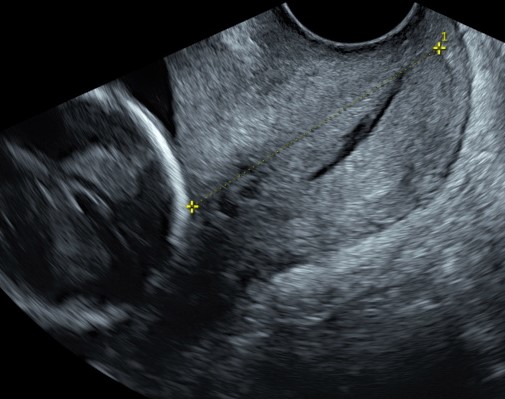

Un passaggio importante è la valutazione del collo dell’utero, che ha la funzione di sorreggere l’utero che cresce con il suo prezioso contenuto. Con l’ecografia transvaginale è infatti possibile ottenere una misurazione della lunghezza della cervice uterine e vedere se sono presenti modificazioni dell’orifizio interno, che sarebbe la porta di ingresso verso l’utero.